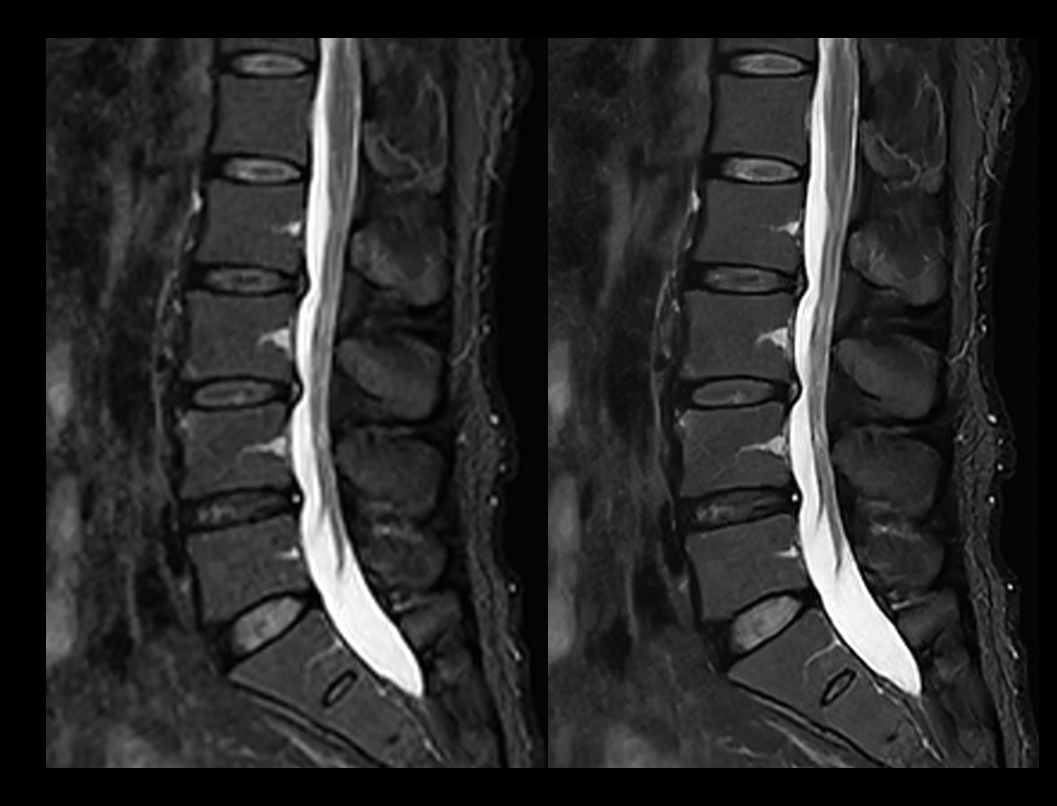

脊柱 T2W STIR

常规成像 (2:44 min) vs. uAIFI DeepRecon™ (2:44 min)

1.11×1.11×4 mm3